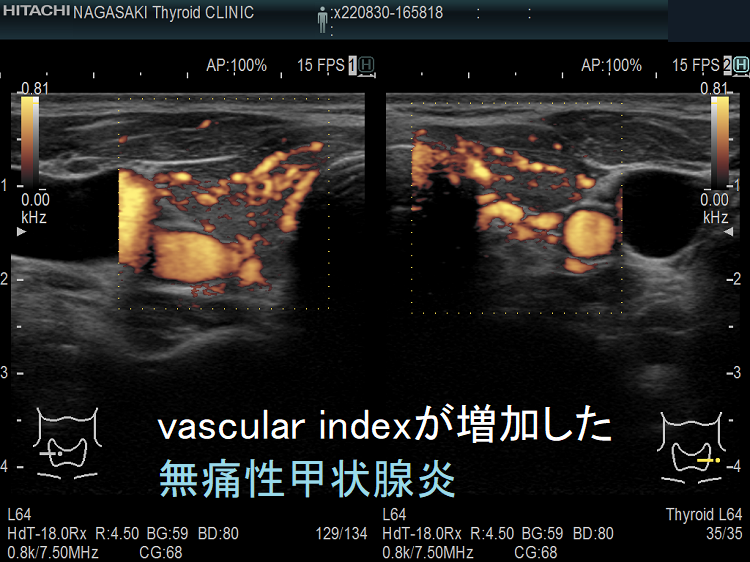

vascular index(血流指数)が増加した無痛性甲状腺炎

vascular index(血流指数)が増加した急性期の無痛性甲状腺炎の下甲状腺動脈の収縮期最大血流速度(ITA-PSV);ITA-PSVは低下しています。

筆者らが、バセドウ病再発・抗甲状腺薬の効き易さ予測目的で開発した下甲状腺動脈の収縮期最大血流速度(ITA-PSV)測定 は、無痛性甲状腺炎と甲状腺機能亢進症/バセドウ病と鑑別するのにも有用です。

無痛性甲状腺炎急性期の下甲状腺動脈収縮期最大血流速度(ITA-PSV)は、正常~低値です。甲状腺機能亢進症/バセドウ病の下甲状腺動脈収縮期最大血流速度(ITA-PSV)は正常~異常高値です。

筆者らが提唱した下甲状腺動脈の収縮期最大血流速度(ITA-PSV)を応用した論文がインドから出ています。甲状腺機能亢進症/バセドウ病と無痛性甲状腺炎を鑑別できる下甲状腺動脈の収縮期最大血流速度(ITA-PSV)のカットオフ値は、30 cm/s(感度91%、特異度89%)としています[Arch Endocrinol Metab. 2019 Sep 2;63(5):495-500.]。

ただ、筆者の経験ではカットオフ値は32.0 cm/s にした方が感度はあまり変わらず特異度が高くなります。特異度は89%程度なので、ITA-PSV 30.0-45.0 cm/s くらいの無痛性甲状腺炎は珍しくありません。むしろITA-PSVのみでバセドウ病と判断すれば診断を誤る可能性があります。

さすがに、ITA-PSV≧50.0 cm/s なら99%バセドウ病のはずです。しかしながら、長崎甲状腺クリニック(大阪)ではITA-PSV≧64.6 cm/sの無痛性甲状腺炎が見つかりました。